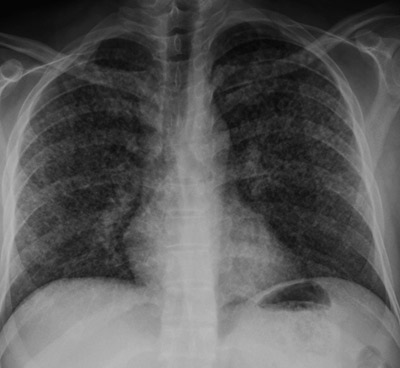

Røntgen thorax viste disseminert utbredelse av smånodulære, stedvis dels konfluerende små fortetninger i begge lunger (fig 1). Grunnet mistanke om smitteførende tuberkulose ble pasienten isolert. Bronkoskopi ble utført.

Differensialdiagnoser til miliære fortetninger fra tuberkulose inkluderer lungemetastaser, sarkoidose, hypersensitivitetspneumoni og pneumokoniose (3). Ved lungemetastaser er miliære fortetninger ved røntgen thorax et uvanlig mønster, og er da som oftest assosiert med høyvaskulære tumorer som nyrecancer, melanom eller thyreoideakarsinom.